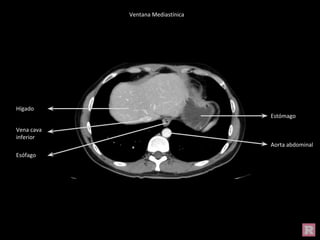

Ventana Mediastínica

Ventana Pulmonar

Hígado

Estómago

Vena cava

inferior

Aorta abdominal

Esófago